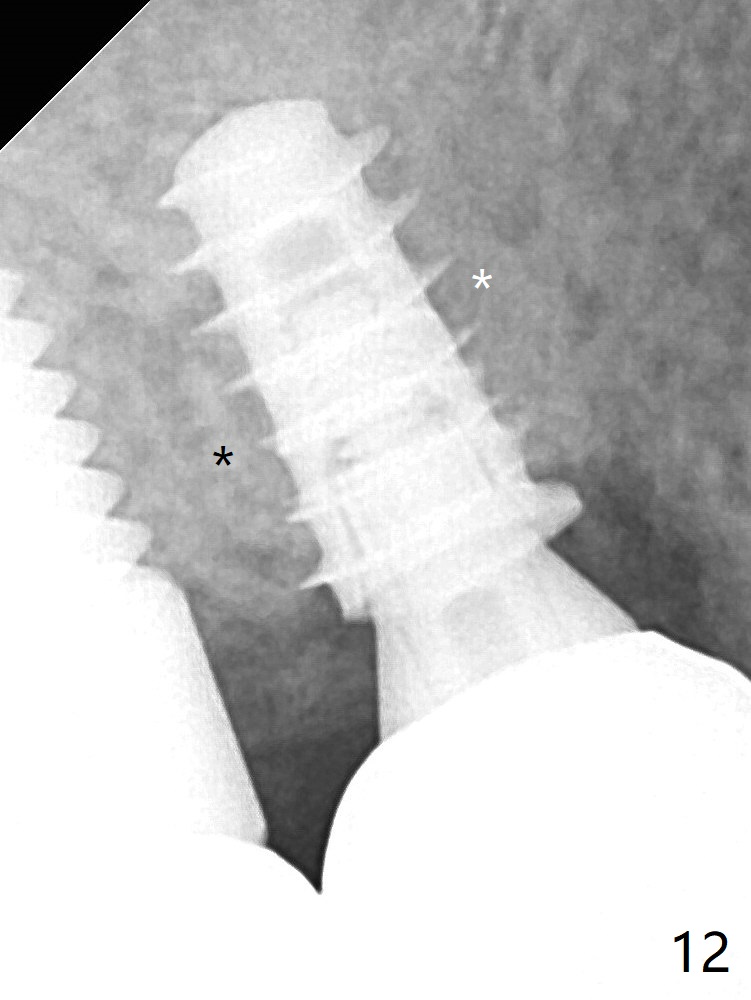

The abutment screw is loose 2.5 months post cementation, but the bone density in the previous mesiobuccal and distobuccal sockets (Fig.12 *) increases.